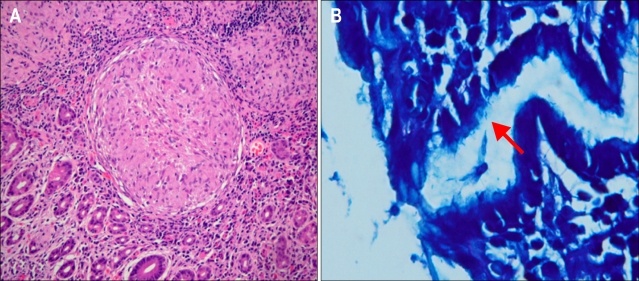

Что такое гранулема? 🧐

Представьте, что иммунная система — это армия, охраняющая ваше тело. Когда она сталкивается с чем-то, что не может быстро уничтожить или «опознать» (например, стойкая бактерия, инородная частица), она поступает мудро: она заключает эту угрозу в прочную капсулу, как в крепость.

Эта микроскопическая «крепость» из иммунных клеток и есть гранулема. Она изолирует проблему, не давая ей распространяться. С одной стороны, это защитный механизм. С другой — сами эти «крепости», появляясь в стенке кишечника, могут вызывать массу проблем.

Золотым стандартом диагностики является эндоскопия с взятием биопсии (маленького кусочка ткани). Мы смотрим слизистую изнутри, а гистологи под микроскопом ищут те самые «крепости». Также помогают МРТ или КТ кишечника, которые показывают утолщение стенки и другие изменения.